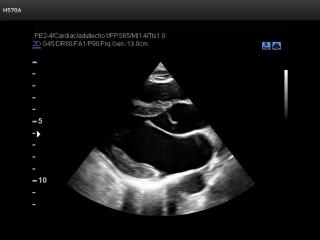

Atlas of ultrasound images - echocardiography

In this section of atlas the results of ultrasonic examinations in cardiology are represented. Here you can see images: aortic, mitral and tricuspid valves, left and right ventricles, echograms of cardiomyopathy, regurgitation of valves, etc.